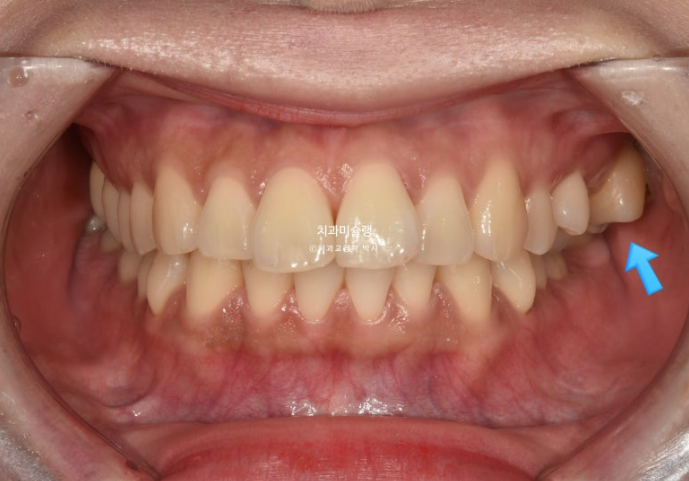

2년 전 교정치료를 위해 온 30대 환자분입니다. 파란 화살표 볼쪽으로 튀어나간 어금니들이 보입니다.

중심선 불일치도 보입니다.

앞니뻗침으로 인한 돌출이 있고

좌측에는 가위교합이 소구치에 하나 대구치에 하나 총 2군데 있습니다.

교합을 담당하는 어금니 중 절반이 가위교합 상태이니, 좌측으로 씹기가 힘든 상태입니다.